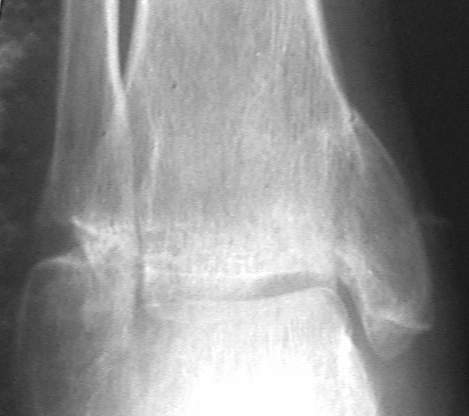

У больного травма в августе 2001 г. Лечился консервативно, Проводилась иммобилизация гипсовой лонгетой 3 мес. В последующем местное лечение. Остается контрактура боли в области наружной лодыжки. Направлен в наше отделение в конце января 2002 г Планируется костная аутопластика, остеосинтез пластиной, винтами перелома наружной лодыжки. Решается вопрос о коррекции неправильно сросшегося перелома внутренней лодыжки. Рентгенограммы: фас; профиль; план Сергей Зырянов

на снимке, кстати, срезан ее дистальный отдел, и правильность взаимоотношений с таранной костью не оценить. Если они правильные - я бы присоединился к мнению об оставлении ее покое.

А вот укорочение внутренней, похоже, привело к натяжению дельтовидной связки и гиперпрессии в медиальном отделе сустава, и уже сейчас там

видно сужение щели. Так что есть смысл обратить внимание на ортопедическую профилактику деформирующего артроза.